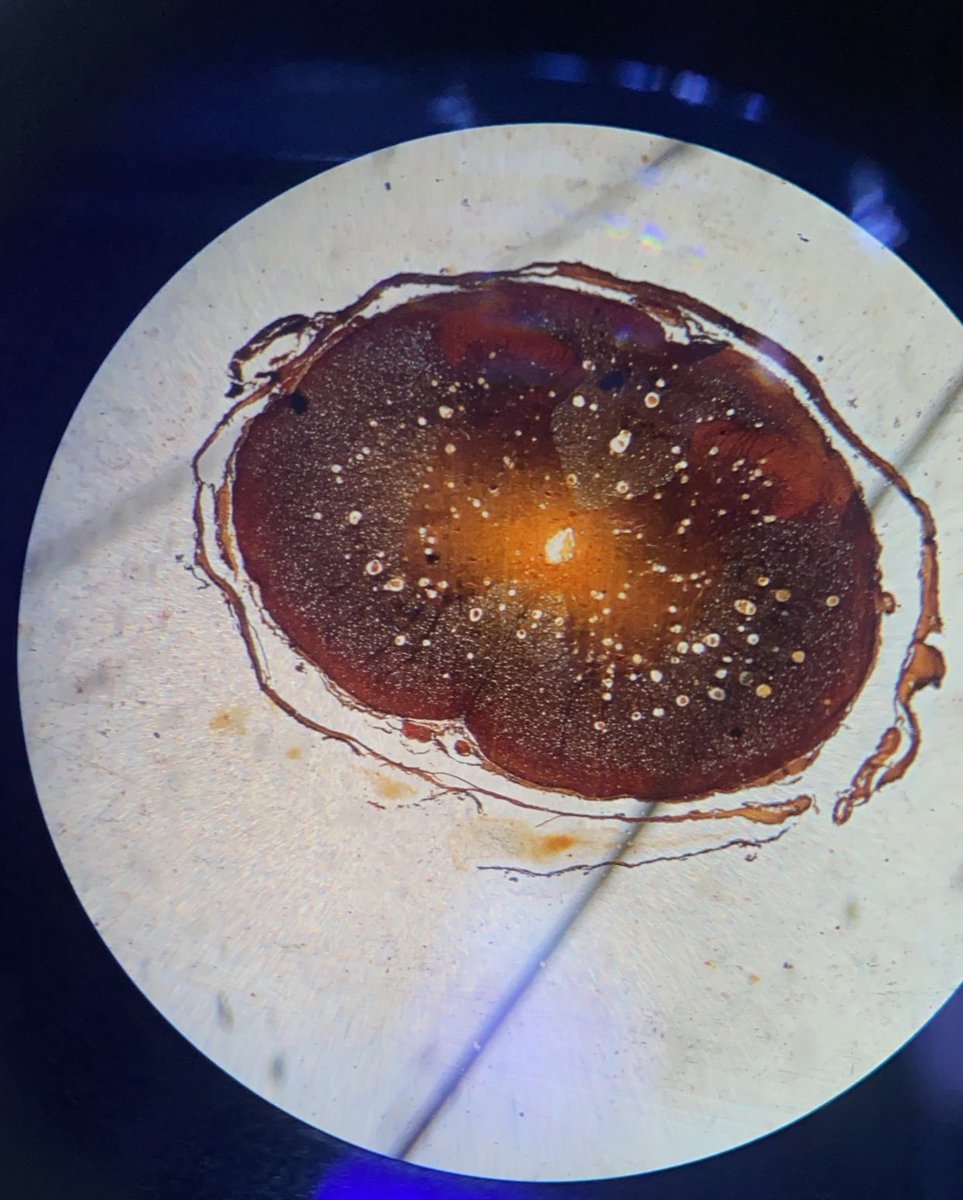

كانت لي فرصة اليوم بالمشاركة في فعالية جيل مبصر في مدارس التربية الإسلامية، تجربة أضافت لي بقدر ما أضفت لها🩵 فحص نظرهم كان خطوة صغيرة لصحة أكبر ومستقبل أوضح 🤩 @OptometryClub